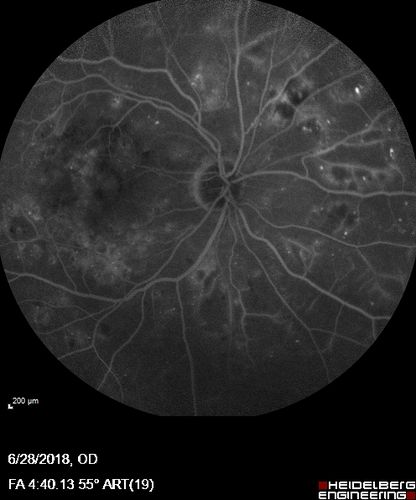

Diabetic Macular Edema with Exudates

Patient did not want injection therapy and did well with laser